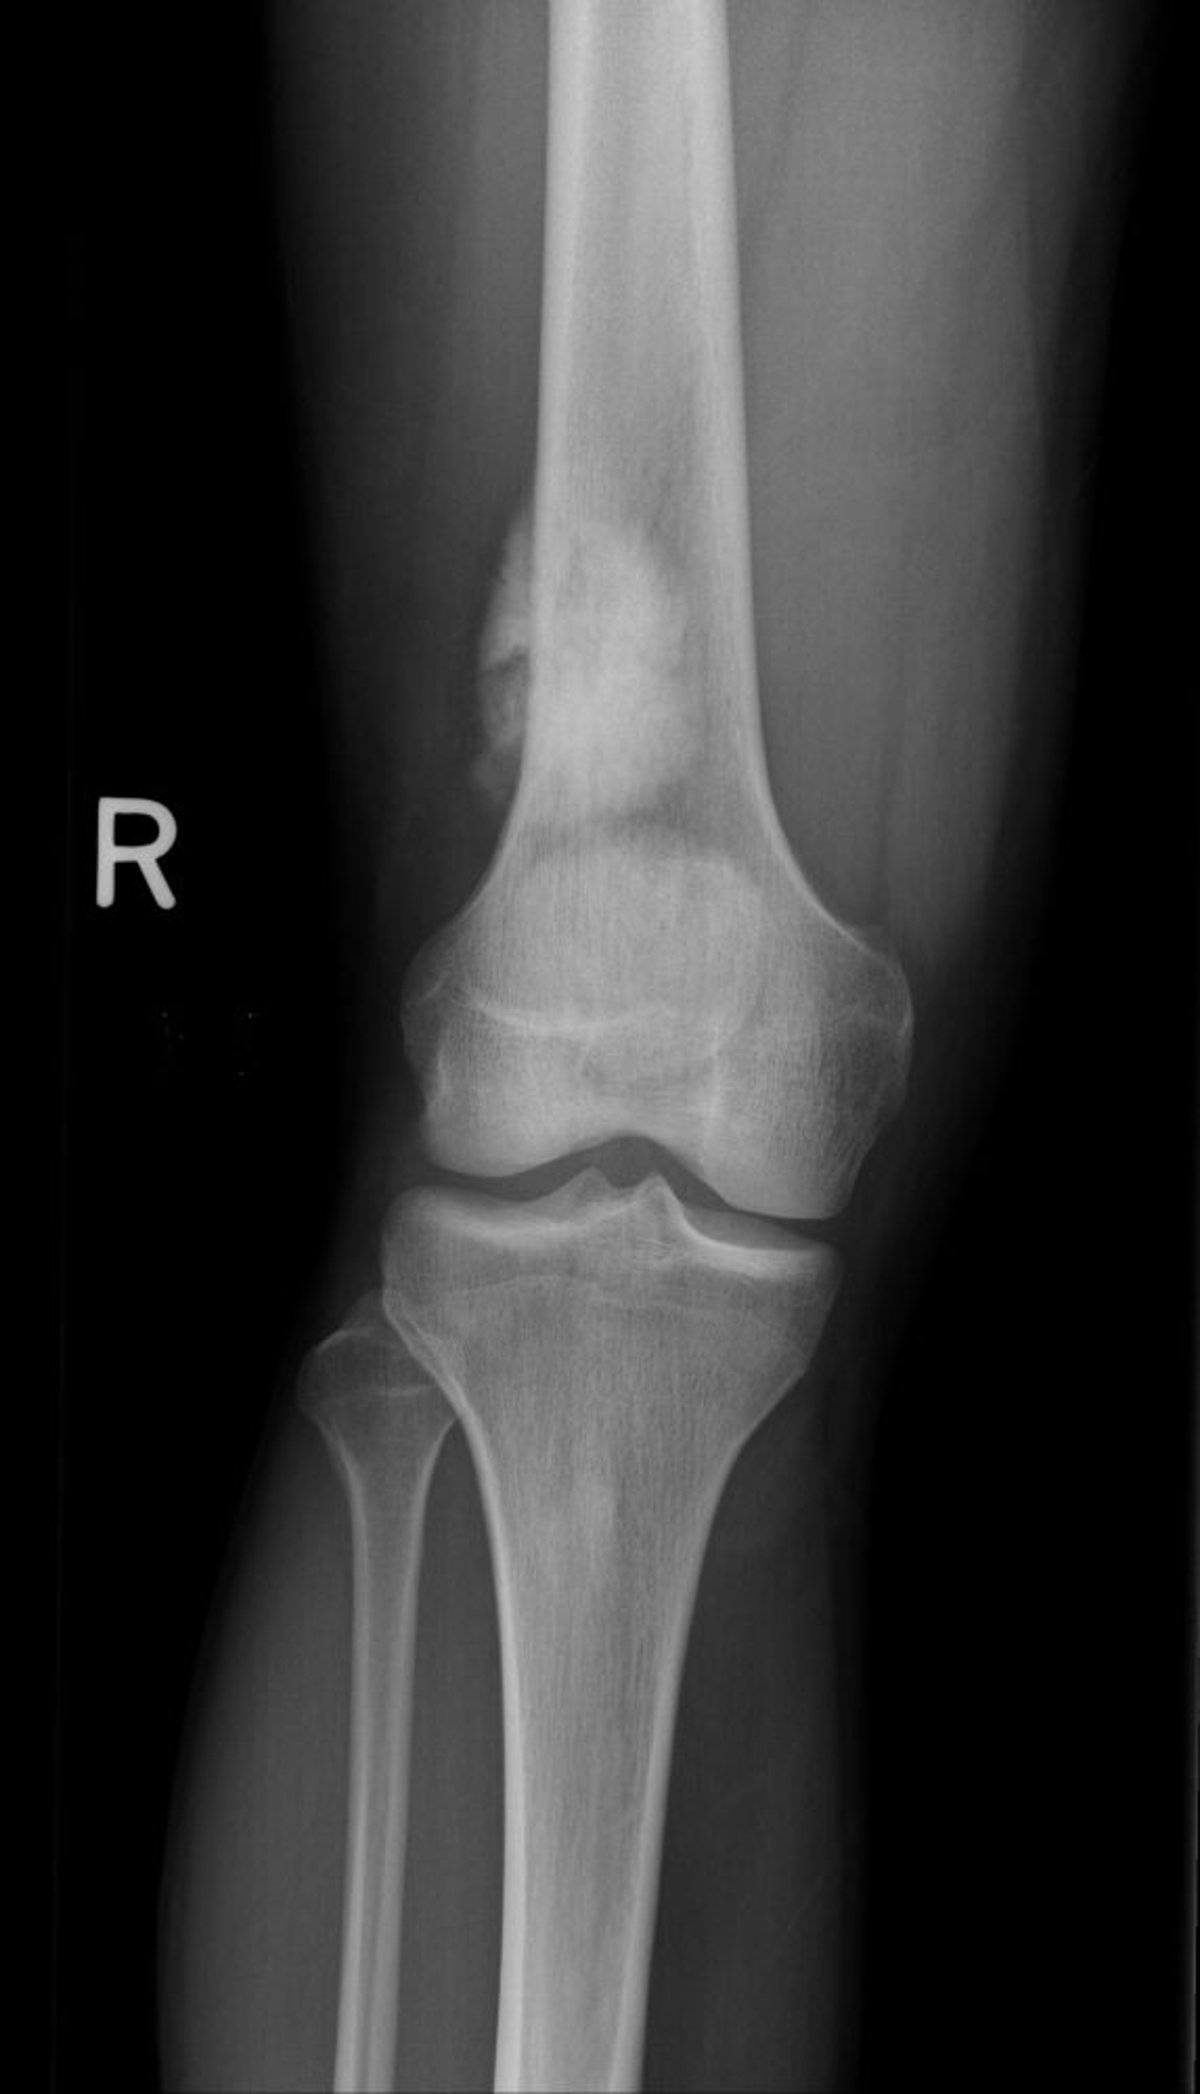

На этой рентгенограмме колена показана остеосаркома бедренной кости выше колена.

Изображение любезно предоставлено д-ром Майклом Дж. Джойсом (Michael J. Joyce) и д-ром Хаканом Иласланом (Hakan Ilaslan).